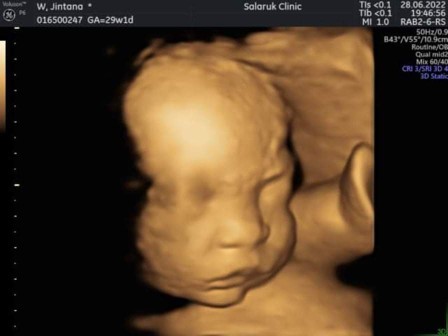

อยากซาวด์ 4 มิติค่ะ ราคาจะแล้วแต่คลินิกหรือเหมือนกันทุกที่เลยหรือเปล่าคะ อยากอ่านประสบการณ์ของแม่ๆที่ไปซาวด์ที่คลินิกด้วยค่ะ ว่าเป็นยังไงบ้าง #ท้องแรกค่ะ

ราคาแล้วแต่คลีนิกค่ะ เห็นลูกชัดเจน ถ้าจะให้ดี 28 วีคขึ้นไปค่ะ น้องจะมีไขมัน มีแก้มแล้ว ดูได้ทุกส่วน ดูปากแหว่งด้วยเพื่อความสบายใจค่ะ หมอซาวด์ให้ครั้งแรก 20 วีค น้องยังเป็นหนังหุ้มกระดูกอยู่ค่ะ

29+0 หมอดูทุกอย่างร่างกาย ความผิดปกติ ดูให้นานมากไม่ชัดเข้ามาดูใหม่อีกรอบ สรุป สองชั่วโมงในการดูหน้าลูกสาวขี้อาย 1500 ค่ะ